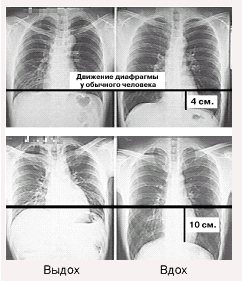

На верхнем снимке показана амплитуда движения диафрагмы обычного среднего человека. При вдохе и выдохе диафрагма у него опускается и поднимается на 4 см .

У людей же, мастерски владеющих йогой, диафрагма поднимается и опускается на 10 см (нижний снимок). Это более чем в два раза превышает показатели обычного человека.

Амплитуда движения диафрагмы непосредственно связана с функцией дыхания. Если амплитуда небольшая, то человек способен только к поверхностному, неэффективному дыханию. И наоборот, когда за счёт дыхательных тренировок происходит увеличение амплитуды движения диафрагмы и вырабатывается глубокое эффективное дыхание, стимуляция внутренних органов усиливается и кровообращение во всем теле существенно улучшается.